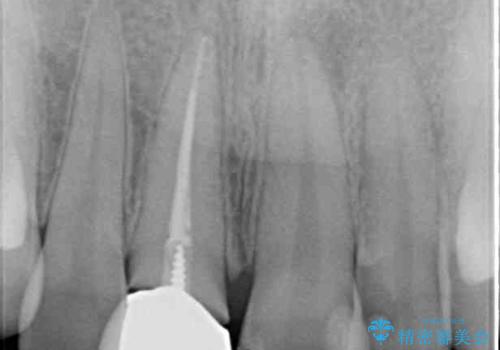

レントゲン写真より、変色してしまった歯は根管治療がされていなかったため、根管治療後にファイバーコアによる土台築製を行い、前歯2本をオールセラミッククラウンにて補綴することとしました。